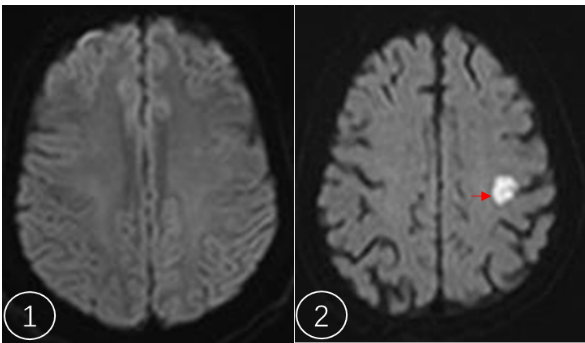

图1 为颅脑正常DWI序列扫描表现

图2为颅脑额叶急性脑梗死DWI序列扫描表现(箭头所指亮白色区域)

DWI 全称“弥散加权成像”(Diffusion-Weighted Imaging),是 MRI(磁共振成像)家族成员,就像是一台超级显微镜,能“看到”水分子扩散运动的快慢。当细胞受损、水肿或密度异常时,水分子的运动就会受限,DWI就能捕捉到这种变化,在图像上呈现为亮白色区域。

这是DWI最出名的应用。当脑中风发生时,脑细胞因缺血缺氧迅速水肿,水分子扩散受限。普通CT和磁共振常规序列在发病早期可能看不出明显异常,但DWI在发病几分钟到几小时内就能清晰显示缺血区域,为抢救争取宝贵时间。